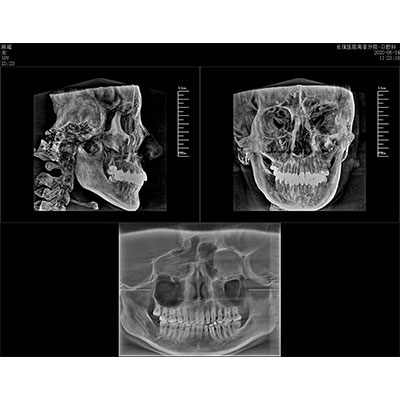

高清口腔三維CT/全景影像 PLX3000A

該款牙科CBCT產(chǎn)品采用動態(tài)平板探測器,獲得三維圖像的同時還具有數(shù)字化全景功能,廣泛應(yīng)用于口腔頜面外科、正畸科、正頜外科、種植科、牙體科、顳下頜關(guān)節(jié)科等術(shù)前術(shù)后。

專有三維重建算法,可提供任意位置高清斷層影像。

可同時觀察軸向面、冠狀面和矢狀面圖像,方便臨床診斷。